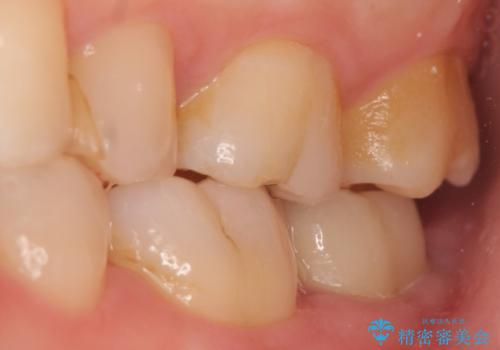

- 左下の一番奥の歯が時折激しく痛むので診て欲しいといらっしゃった方の症例です。以前に他院を受診したところ、そもそも被せ物を入れるスペースがないため抜歯しかないと言われたとのことでした。

診査の結果根尖病変を認めたため再根管治療を行った後に、被せ物を入れるスペースを作るため歯冠延長術を行いました。